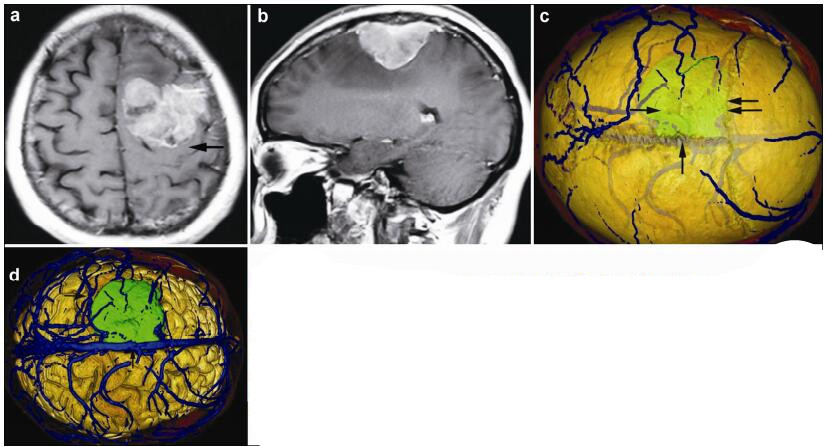

20170308100624  Figure 4 Magnetic resonance imaging and reconstruction images in a 36-year-old female patient with a meningioma in left frontal lober. (a, b) T1 enhancement scans: The tumor presented as heterogeneous enhancement and locates anerior to left postcentral gyrus (horizontal single arrow). (c) 3D reconstruction (skull semitransparent): The tumor (horizontal single arrow) located behind the coronary suture (horizontal double arrow) and adjacent to sagittal suture (vertical single arrow). (d) 3D reconstruction (do not show the skull): The tumor locates anterior to the left postcentral gyrus (vertical single arrow) and the right side of the tumor is adjacent to the superior sagittal sinus (vertical single arrow).